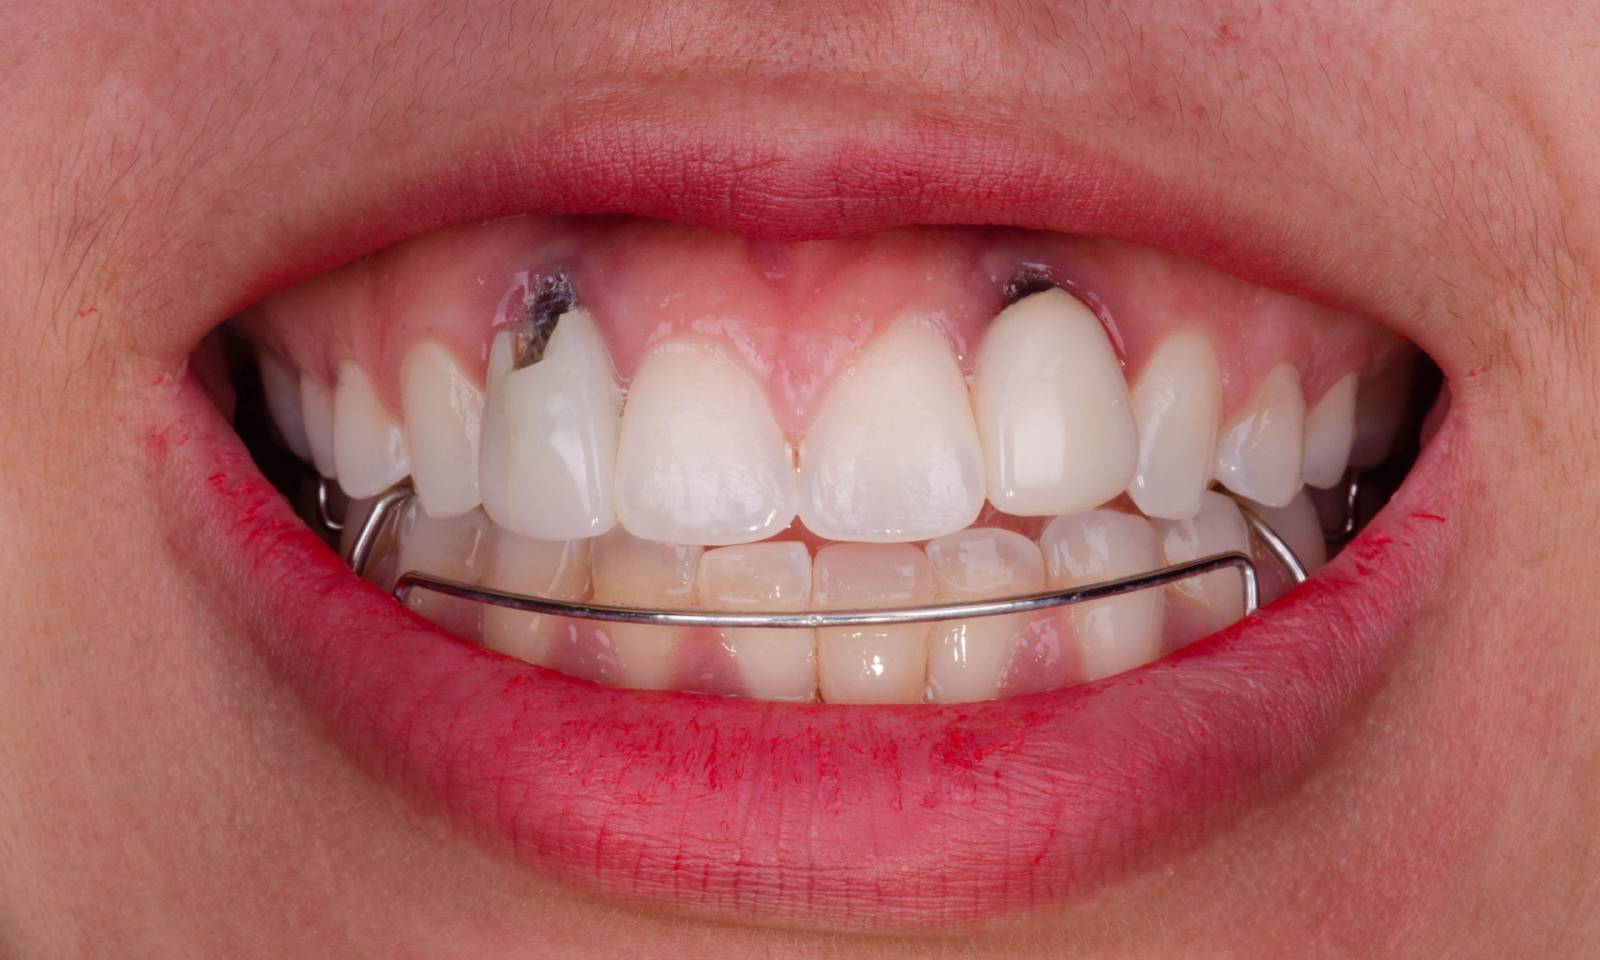

Upper central incisors, in 4 hours

Four IPS e.max CAD single crowns

The restoration with all-ceramic crowns did not require subgingival preparation to cover the margin and no dark metal shadows disturbed the esthetics. With CEREC Primescan and CEREC Primemill patients receive a high-quality all-ceramic restoration faster than ever before.

Before: Inadequate fillings on teeth 12-22, an uneven gingival line on 12 and 11 and incisal edges severely eroded.

After: Four highly esthetic and individualized lithium disilicate ceramic crowns.

Claudia Scholz

Kiel, Germany